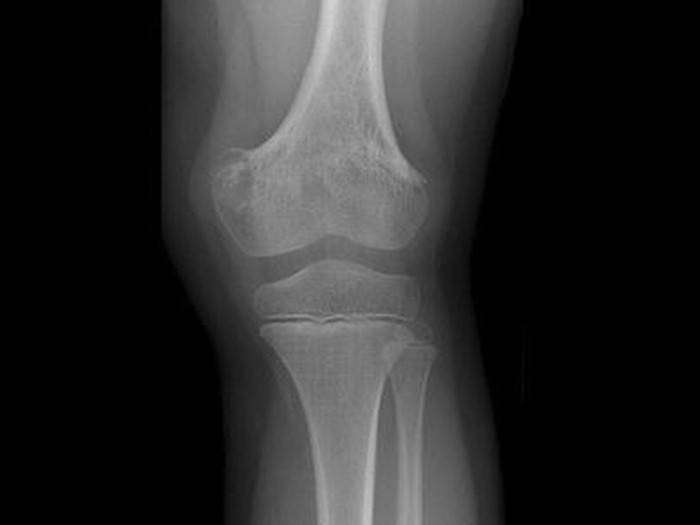

Рентгенография является подспорьем только после двух недель болезни. В зоне воспаления просматривается разрежение ткани, нечеткость костных контуров. Характерен линейный периостит – нечеткая тень, параллельная поверхности кости. Затем начинается некроз костной ткани с образованием секвестров.

Постепенно на снимках становится очевидным склерозирование, остеопороз и проявления периостита. Это говорит об уменьшении остроты и хронизации процесса.